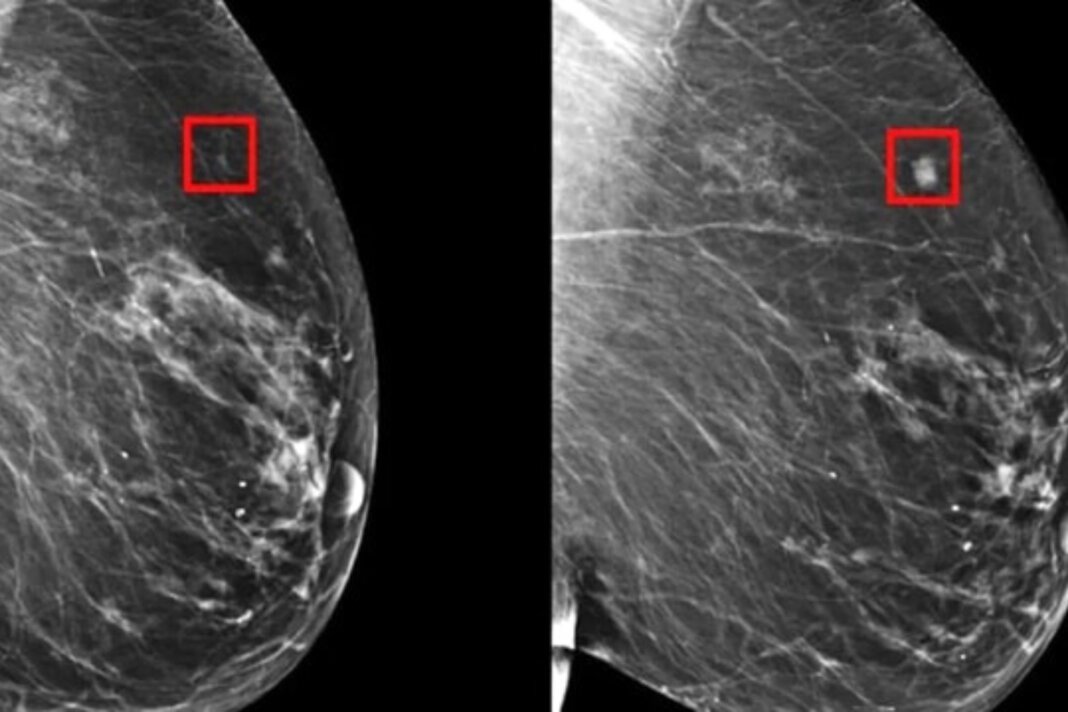

Sul punto: L’intelligenza artificiale può rilevare il cancro al seno con cinque anni di anticipo